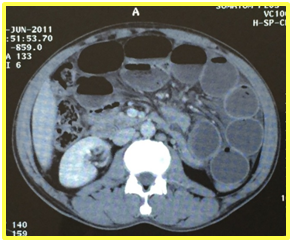

A naso-gastric tube was placed on suction. There was no clinical improvement and surgical intervention was immediately prepared: the bowel obstruction was related to a mesenteric mass at which the small bowel and sigmoid colon were clustered and contiguous with dilation of the small bowel upstream. We performed a resection of the small bowel and sigmoid colon with the mesenteric mass. Pathological examination of the surgical specimen found a colonic tuberculosis fistulized in the mesentery (Figure 2).

Figure 2: Histopathologic image of an epithelioid granulomas with central necrosis at colon.